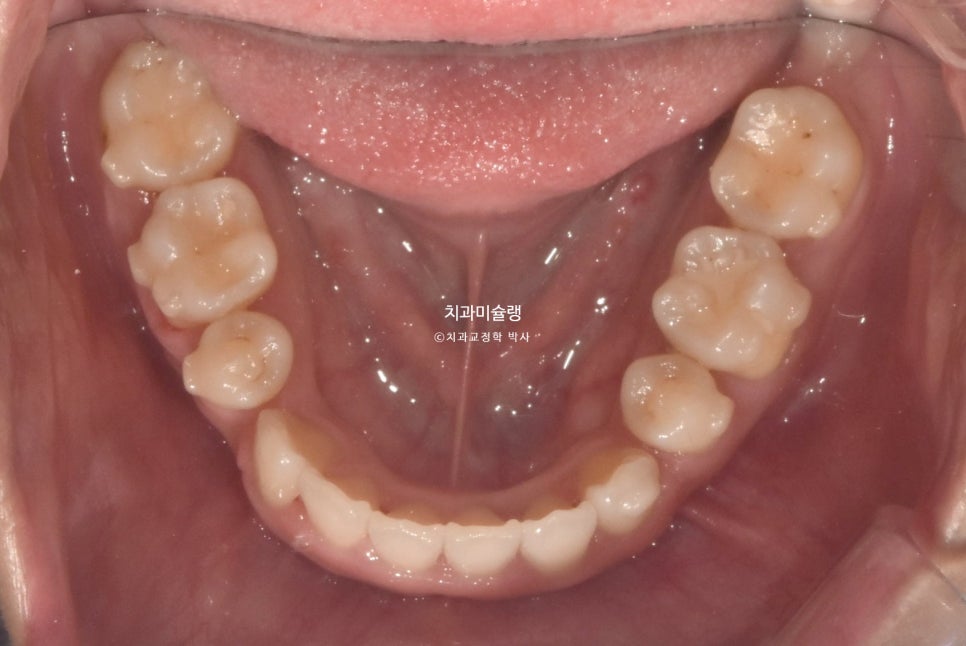

악궁이 소구치 부위가 안으로 쓰러져 찌그러진 모양입니다.

앞니뿐 아니라 어금니에도 여기저기 충치가 보입니다.

총생 (치아 삐뚤한 정도) 가 심하고 돌출감도 있어 작은어금니 4개 발치가 불가피한 상황입니다.